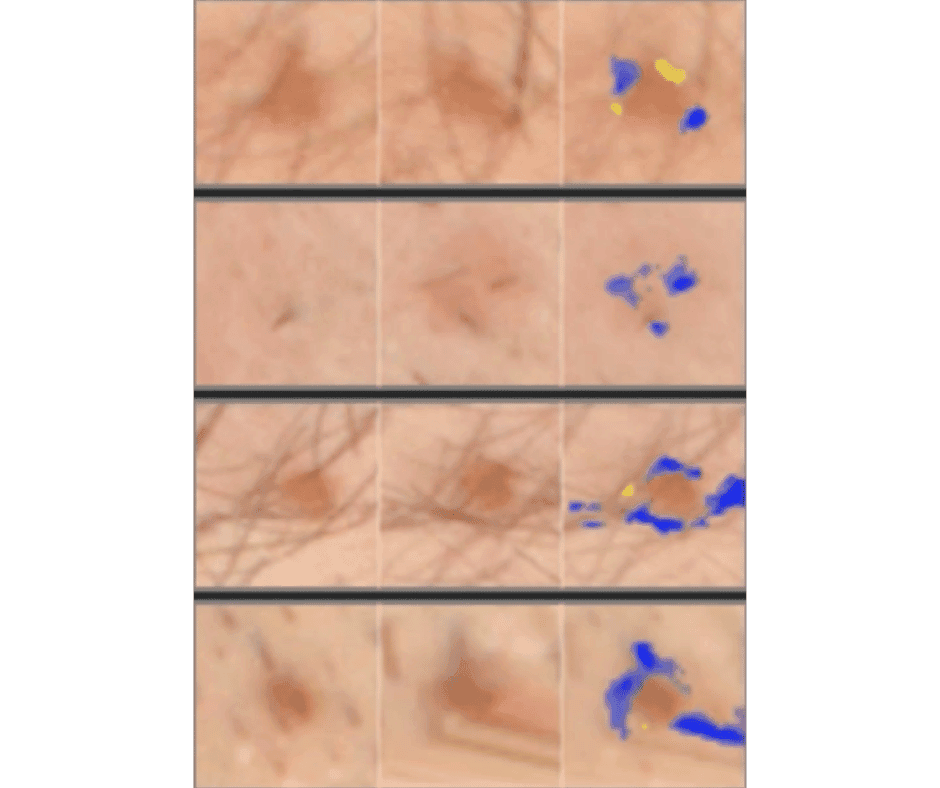

Our technology uses artificial intelligence to analyze skin images with remarkable precision. Unlike traditional visual inspections, our AI can detect subtle patterns and changes that might not be visible to the naked eye.

AI learns through pattern recognition, similar to how children learn to identify objects. By analyzing thousands of skin images, our AI has learned to recognize the visual characteristics of different skin conditions, including potential skin cancers.

Pattern recognition

Feature extraction

Change detection

Identifies subtle changes